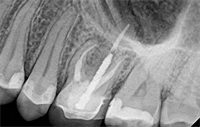

Root canal retreatment is traditionally consider an “all or none” treatment approach. Meaning, all restorative and obturation material must be removed from the entire root canal space of all roots regardless of individual periapical health. In contrast, surgical endodontics is not viewed as an “all or none” approach. It is a generally accepted that only the diseased root(s) should be addressed via root end resection and root end filling. Knowledge gained from CBCT imaging has introduced a new reasonable treatment option for endodonticaly treated teeth presenting with post treatment disease. This new concept allows the clinician to make predictable treatment decisions based on the periapical status of an individual root(s) rather than make assumptions about the tooth as a whole. A “selective root retreatment” combines the approach of an orthograde retreatment with the selectivity of a retrograde surgical root resection. It is being suggested that retreatment could be limited to a single root or roots clearly demonstrating periapical pathology while leaving the root(s) with no visible or perceived pathology untouched.